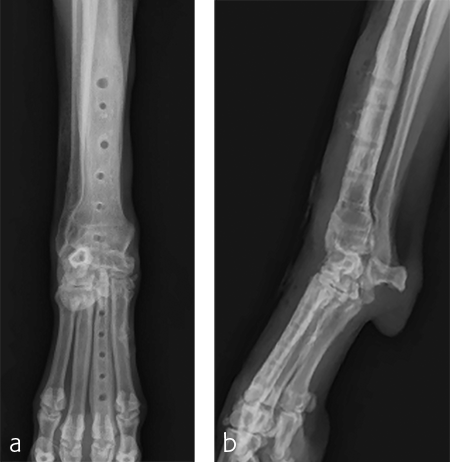

A custom fiberglass palmar splint was applied from the paw to just distal to the elbow after surgery. The splint was used for 4 weeks followed by a soft padded bandage for 4 weeks. Bandage changes were performed weekly. Activity was restricted to leash walks only for 12 weeks postoperatively. Radiographic examination 8 weeks after surgery revealed early healing of the pancarpal arthrodesis and stable implants. No complications were noted (Fig 6).

The patient was returned to normal activity 4 months after surgery. Radiographic examinations at 6 and 6.5 months after surgery revealed stable implants and fusion of the carpus (Fig 7 and 8). Functional outcome was excellent 1 year postoperatively. The patient had returned to full weight-bearing without lameness and the carpus was pain-free and stable.